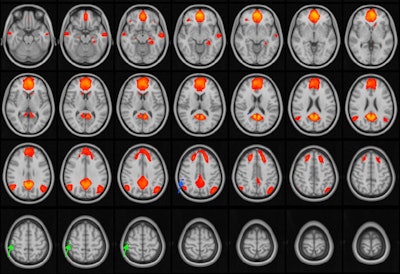

MRI images of the brain with the default mode network highlighted in orange/red. The default mode network is active during periods of wakeful rest, when the mind is not focused on a particular task. The green and blue arrows point to areas of the network that are disrupted in adolescent patients with concussions. Image and caption courtesy of the RSNA.Public awareness of the long-term effects of concussion has increased, as has research regarding these effects, Johnson noted. But there has been little research on the topic using fMRI.

The researchers found no differences in connectivity in the default mode network in patients who had one or two concussions compared with healthy controls. But those who had a history of three to five concussions did have disruptions in the network that were not seen in those who did not.